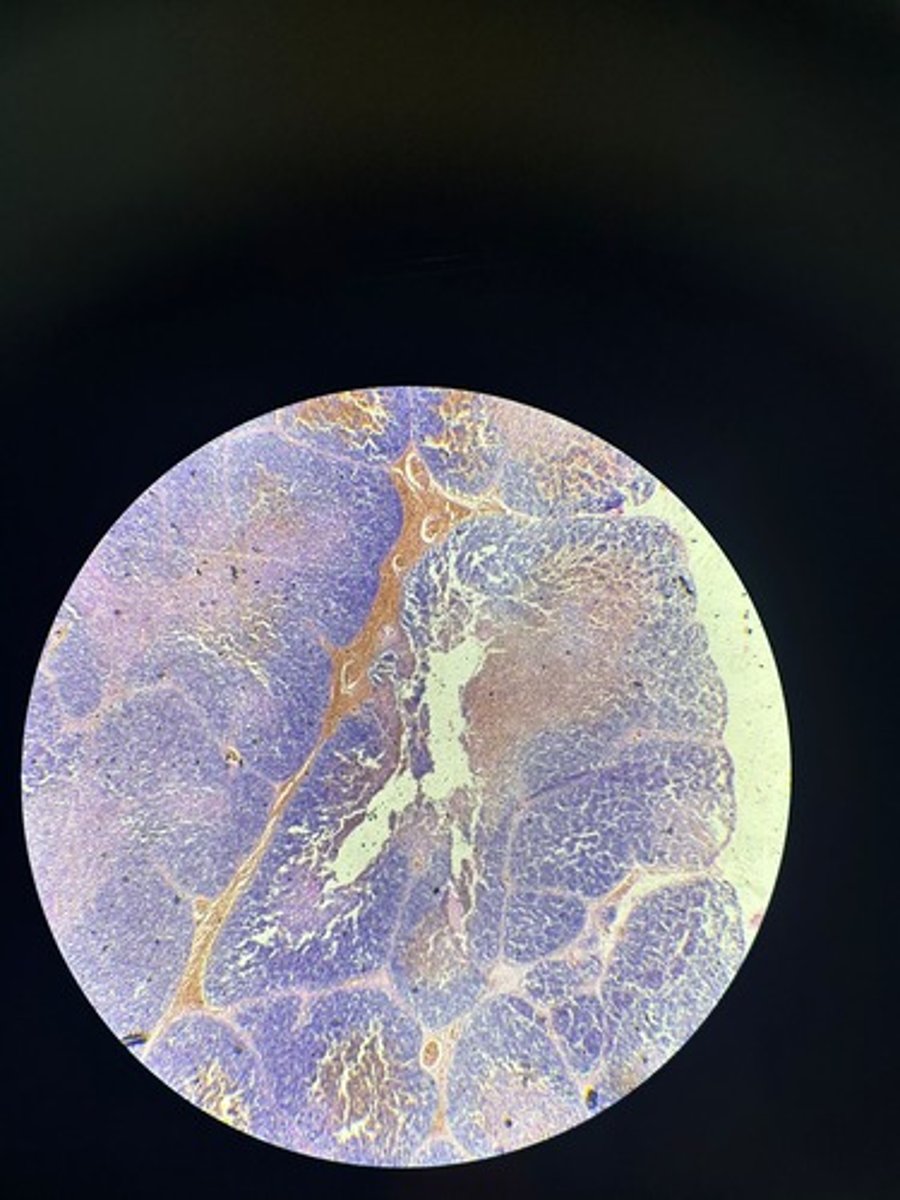

Thymus HE

Thymus HE

Thymus HE

Thymus HE

Thymus HE

Thymus HE

Thymus HE

Thymus HE